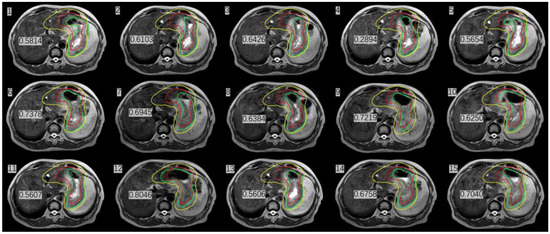

Figure 3.

MRI scans before and after treatment at three different fractions and the red line indicates the whole stomach.